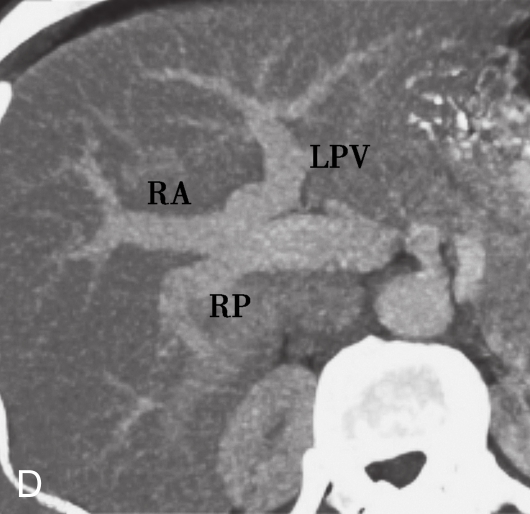

A.冠状面增强CT造影;B.模拟图;C.肝门静脉的三种常见解剖结构;D.Ⅱ型变异:增强造影CT显示肝门静脉分叉成右后、右前肝门静脉和左肝门静脉;E.Ⅲ型变异:增强造影CT显示来自门静脉主干的右后支。

LPV.肝门静脉左支;RPV.肝门静脉右支;RA.右前支;RP.右后支;PV.门静脉;SV.脾静脉;SMV.肠系膜上静脉。